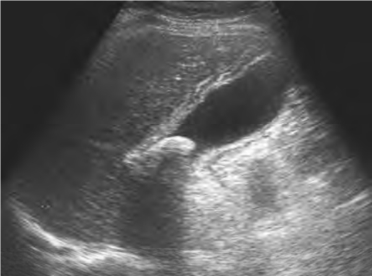

(1)胆囊增大,外形紧张饱满,短轴径>4cm或长轴切面呈短椭圆形(图25-4)。

(2)胆囊壁弥漫性增厚,多数厚度>5mm,水肿,呈双层回声,即“双边影”(图25-4)。

(4)胆囊结石急性炎症发作时,可见结石的超声表现,常位于胆囊颈部(图25-4),应注意寻找。

图25-4 急性胆囊炎结石嵌顿声像图